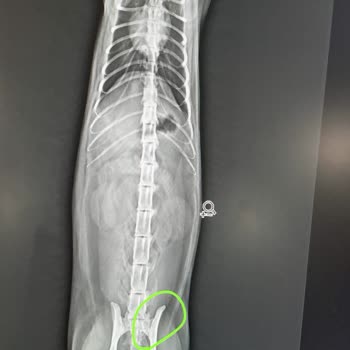

Batman pati pet veteriner'inden şikayetçiyim. Kedim 4. Kattan düştü ve götürdüğüm zaman sadece iğne vuruldu ve bana ısrarla kedinizin hiçbir şeyi yok denildi, içim rahat etti. Fakat sonraki gün kötüleşince diğer veterinere götürdüm, iç organları patladı denildi ve sadece bir gün yaşayıp öldü. Röntge...